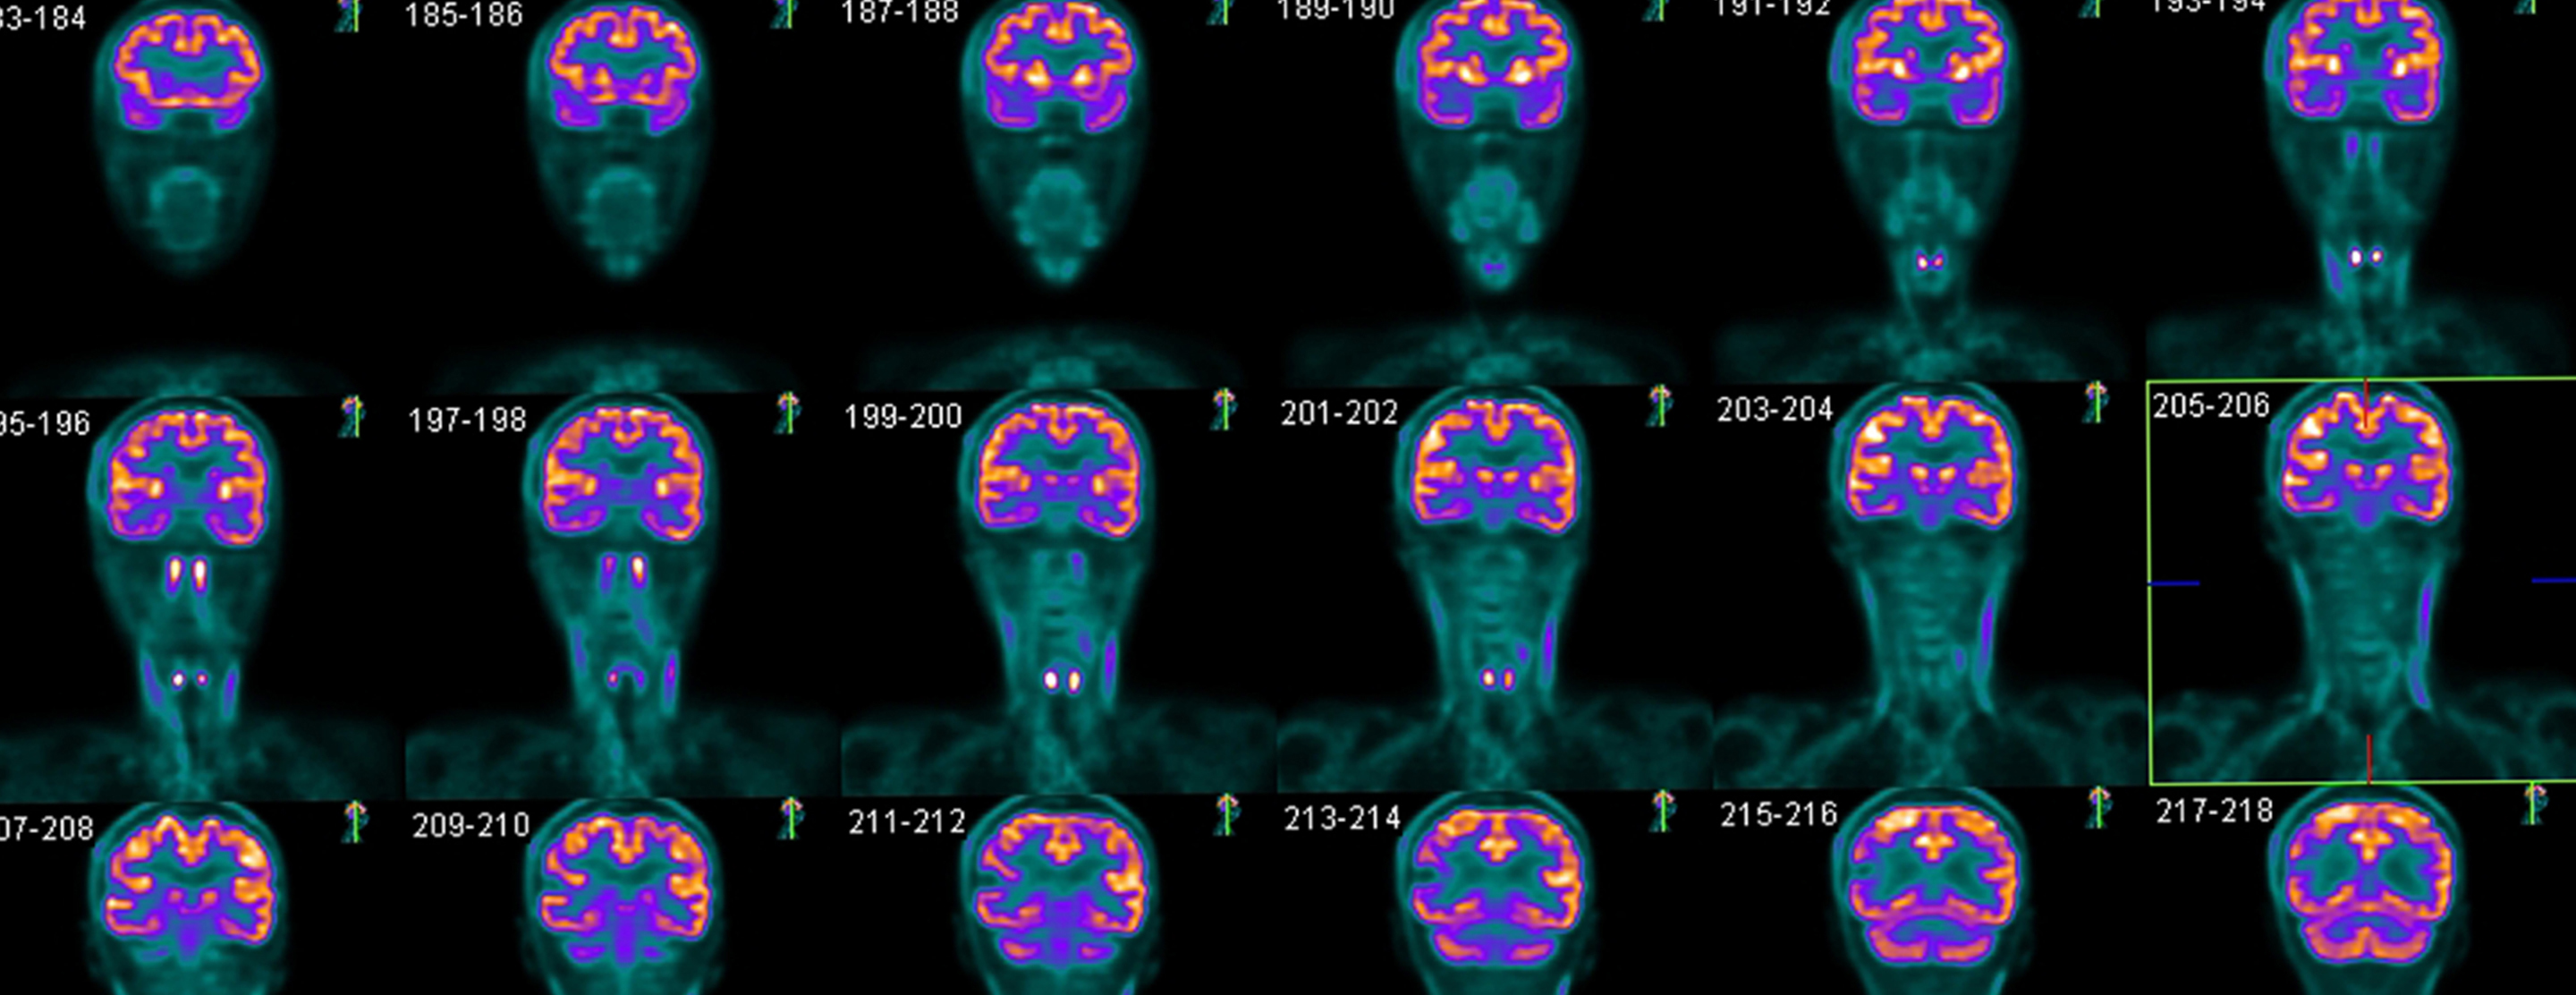

Brain PET scan

A brain positron emission tomography (PET) scan is an imaging test of the brain. It uses a radioactive substance called a tracer to look for disease or injury in the brain.

Then, you lie on a narrow table, which slides into a large tunnel-shaped scanner. The PET scanner detects signals from the tracer. A computer changes the results into 3-D pictures. The images are displayed on a monitor for your provider to read.

A PET scan can show the size, shape, and function of the brain, so your doctor can make sure it is working as well as it should. It is most often used when other tests, such as MRI scan or CT scan, do not provide enough information.

There are no problems detected in the size, shape, or function of the brain. There are no areas in which the tracer has abnormally collected.